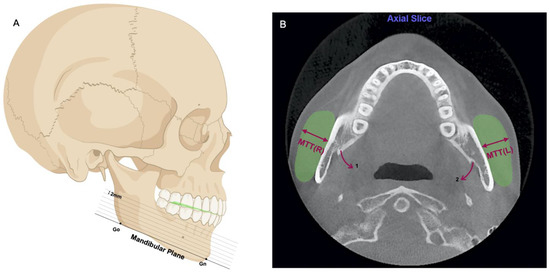

2.3.1. Masseter Muscle Index

2.3.2. Dental and Occlusal Indexes